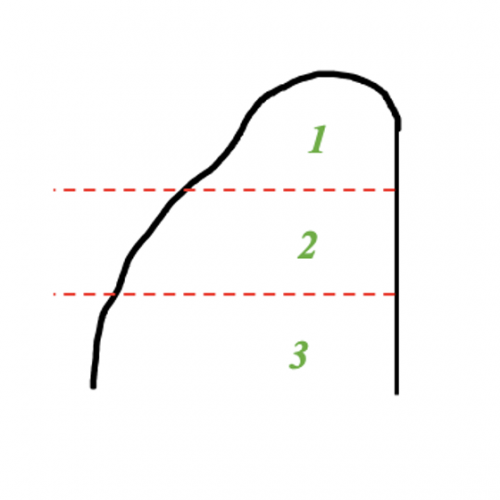

I overpack the cavity with amalgam. This allows easy carving and shaping. When I carve I try to imagine the cusps in three planes as shown below.